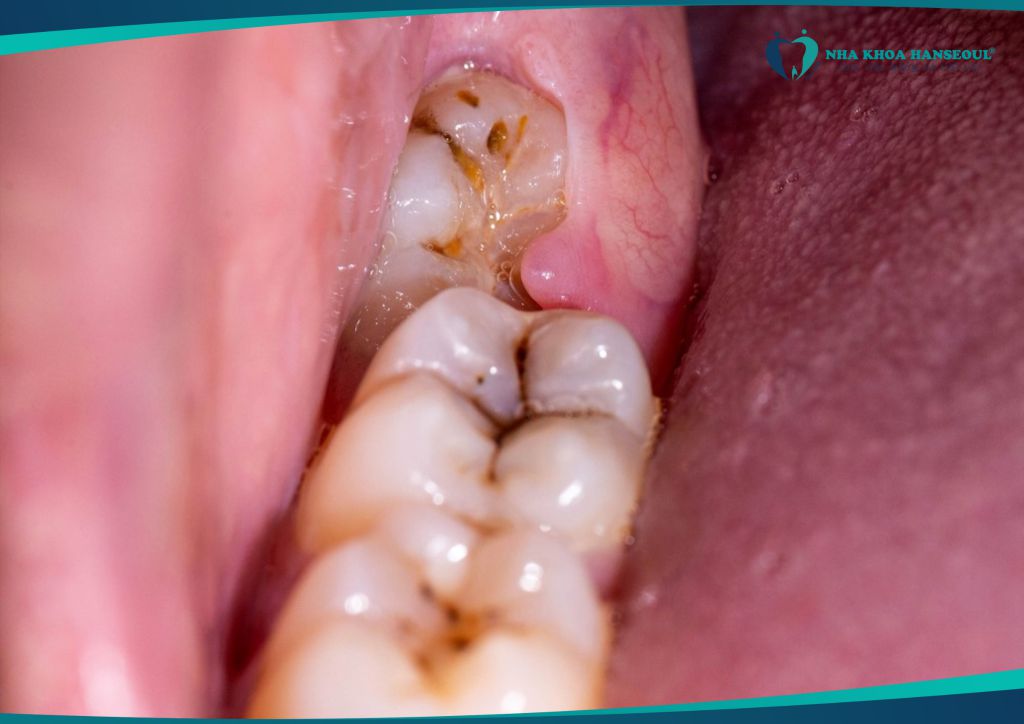

2.2 Viêm lợi trùm – nhiễm trùng lan rộng

Răng khôn chỉ mọc một phần (mọc kẹt), mô nướu phủ bên trên dễ bị vi khuẩn tấn công, gây:

- Sưng tấy, đau nhức dữ dội

- Sốt nhẹ, nổi hạch

- Hơi thở có mùi hôi

Trường hợp nặng có thể lan rộng sang má, vùng cổ, gây áp xe nguy hiểm.